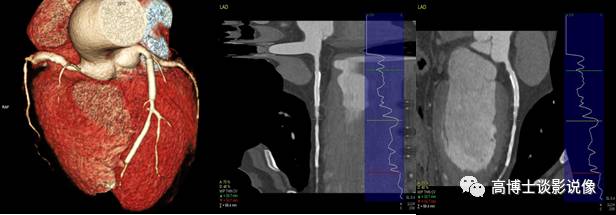

七、冠状动脉支架评估

冠状动脉VR图像立体、直观地显示冠状动脉的各分支、支架的形态。CPR重建显示支架腔内的情况,根据支架内的充盈程度和支架远端的开放程度来判断支架有无再狭窄及狭窄的程度。此例显示:左前降支近段、中段支架植入术后,管腔尚通畅,两支架间及中段支架远端开口处钙化斑块,管腔轻-中度狭窄。